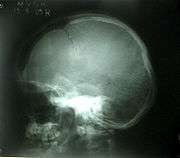

Depressed skull fracture.

A depressed skull fracture is a type of fracture usually resulting from blunt force trauma, such as getting struck with a hammer, rock or getting kicked in the head. These types of fractures—which occur in 11% of severe head injuries—are comminuted fractures in which broken bones displace inward. Depressed skull fractures present a high risk of increased pressure on the brain, or a hemorrhage to the brain that crushes the delicate tissue.

Compound depressed skull fractures occur when there is a laceration over the fracture, putting the internal cranial cavity in contact with the outside environment, increasing the risk of contamination and infection. In complex depressed fractures, the dura mater is torn. Depressed skull fractures may require surgery to lift the bones off the brain if they are pressing on it by making burr holes on the adjacent normal skull.[7]